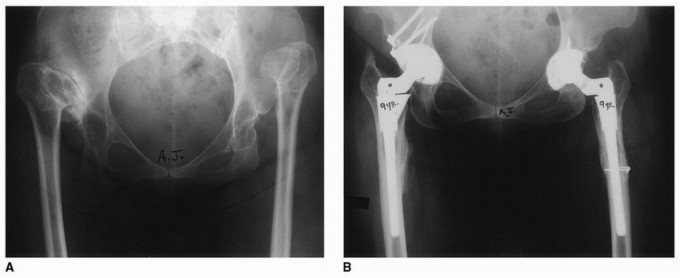

Radiographic Evaluation and Templating

Plain radiographs must include an anteroposterior (AP) projection of the pelvis, an AP of the involved hip, and a Lauenstein (frog-leg) lateral x-ray. Radiographic magnification markers (typically a 25 mm or 30 mm sphere) taped to the involved hip at the level of the greater trochanter allow for an accurate estimate of x-ray magnification. This permits precise digital templating of the femoral canal.

Templating a modular stem is a sequential process:

1. Distal Fixation: The distal stem is templated first to ensure adequate cortical contact (typically 4-6 cm of scratch fit in the diaphysis) while bypassing any stress risers or deformity apices by at least two cortical diameters.

2. Proximal Fill: The proximal body is then templated to fill the metaphysis and reconstitute the medial calcar.

3. Offset and Length: The modular neck or proximal body geometry is selected to recreate the center of rotation, horizontal offset, and leg length.

Computer tomography (CT) scans are rarely indicated for routine THA but are invaluable in complex cases to provide a highly accurate assessment of native femoral anteversion, precise femoral canal dimensions, and acetabular bone stock. Scanograms or full-length standing AP radiographs of the lower extremities may be useful to more accurately assess true limb length inequalities and global coronal alignment.